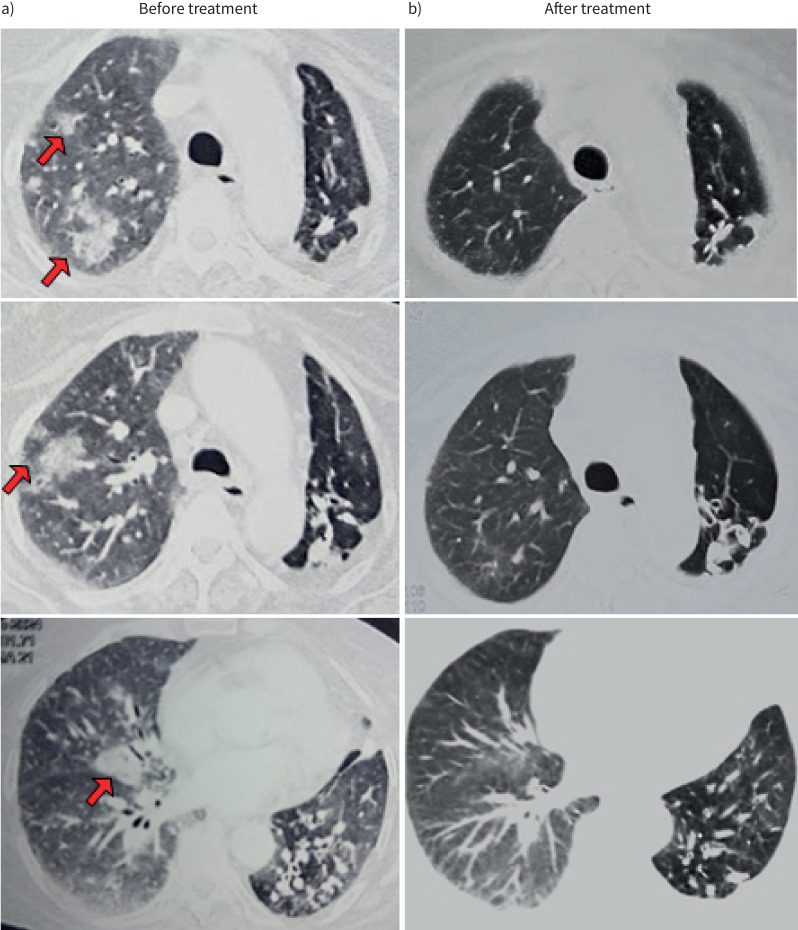

支气管肺泡灌洗检查作为诊断肺圆线虫病的重要工具,在粪便检查为阴性的情况下,寄生虫https://bit.ly/4kuMFMH。

Bronchoalveolar lavage examination as an important tool for diagnosing pulmonary strongyloidiasis in cases where a stool examination is negative for the parasite https://bit.ly/4kuMFMH.